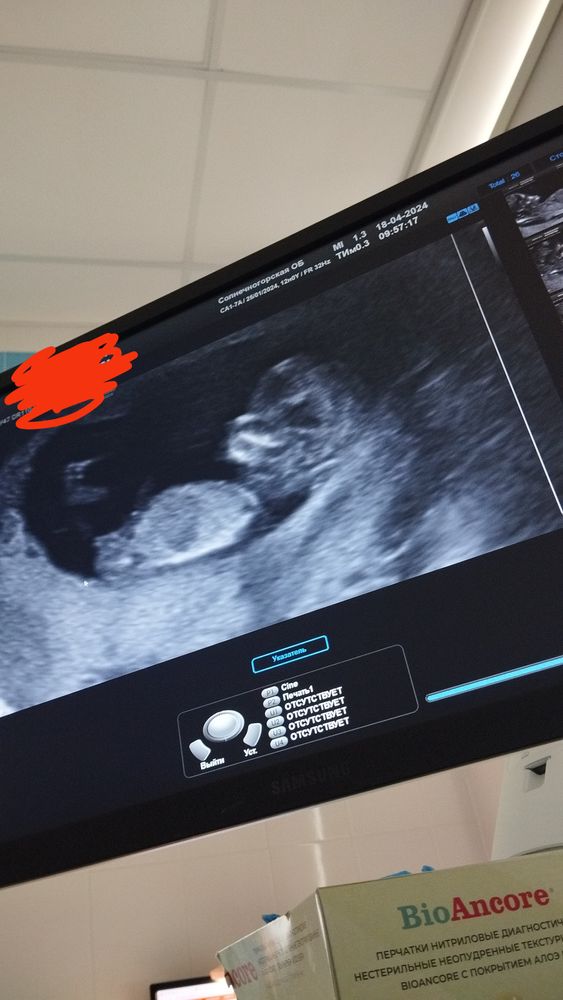

Узи 12 недель .Мальчик или девочка?

Мне кажется девочка. Но фото не совсем удачное)

50 на 50😁